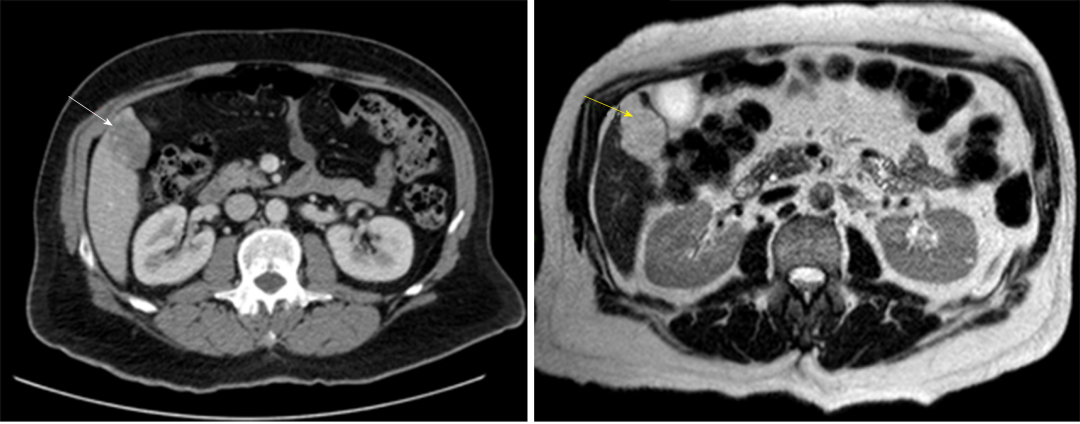

图3 腹部CT造影(白色箭头)和MRI T2加权扫描(黄色箭头)